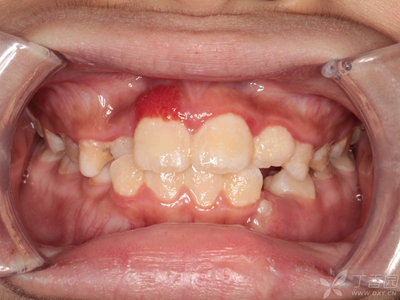

牙龈炎是发生于牙龈组织的炎症,患者可出现牙龈出血伴肿胀、发红、正常形态改变和偶尔不适等症状。本病主要由口腔卫生状况差导致,包括口腔不洁、牙菌斑等,诊断依据临床检查,治疗包括专业牙齿清洁和加强家庭口腔卫生。

牙龈炎可先引起牙齿与牙龈之间的沟(龈沟)加深,然后牙龈充血,炎症围绕一个或多个牙齿,伴牙龈乳头肿胀和易出血。一般无痛,可自行消退,也可维持轻度炎症数年。